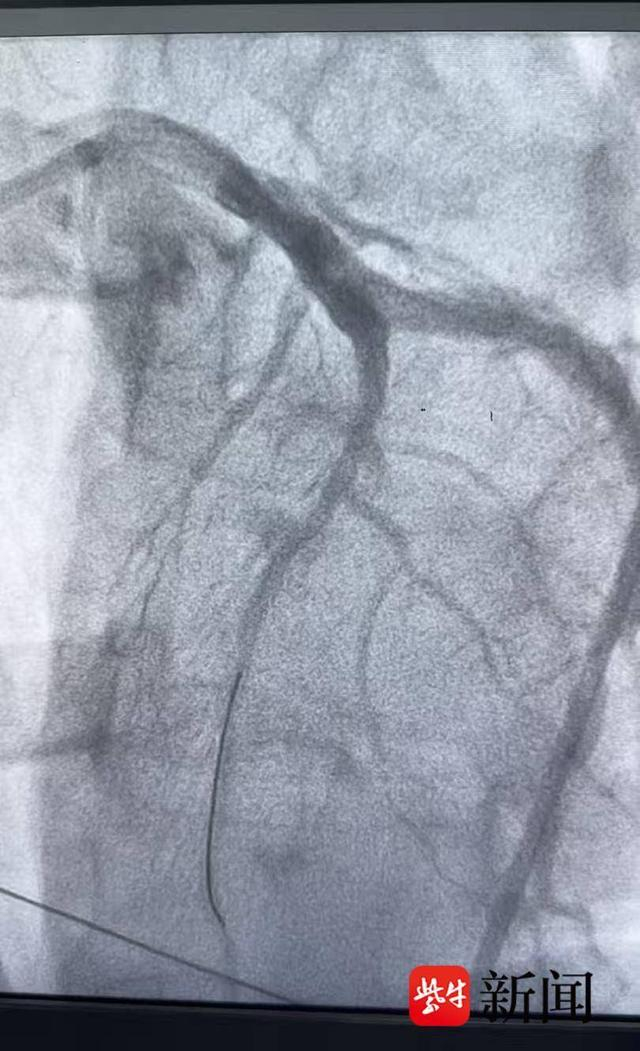

患者被紧急转运至苏州市吴中人民医院后,立即接受急诊冠状动脉造影检查,明确为急性心肌梗死相关血管闭塞。吴中人民医院孙中奇医师迅速为患者实施急诊介入治疗,成功开通闭塞血管,患者术后恢复良好。经过规范治疗与监护,患者病情稳定,已于12月16日顺利出院。

血管开通前

血管开通后